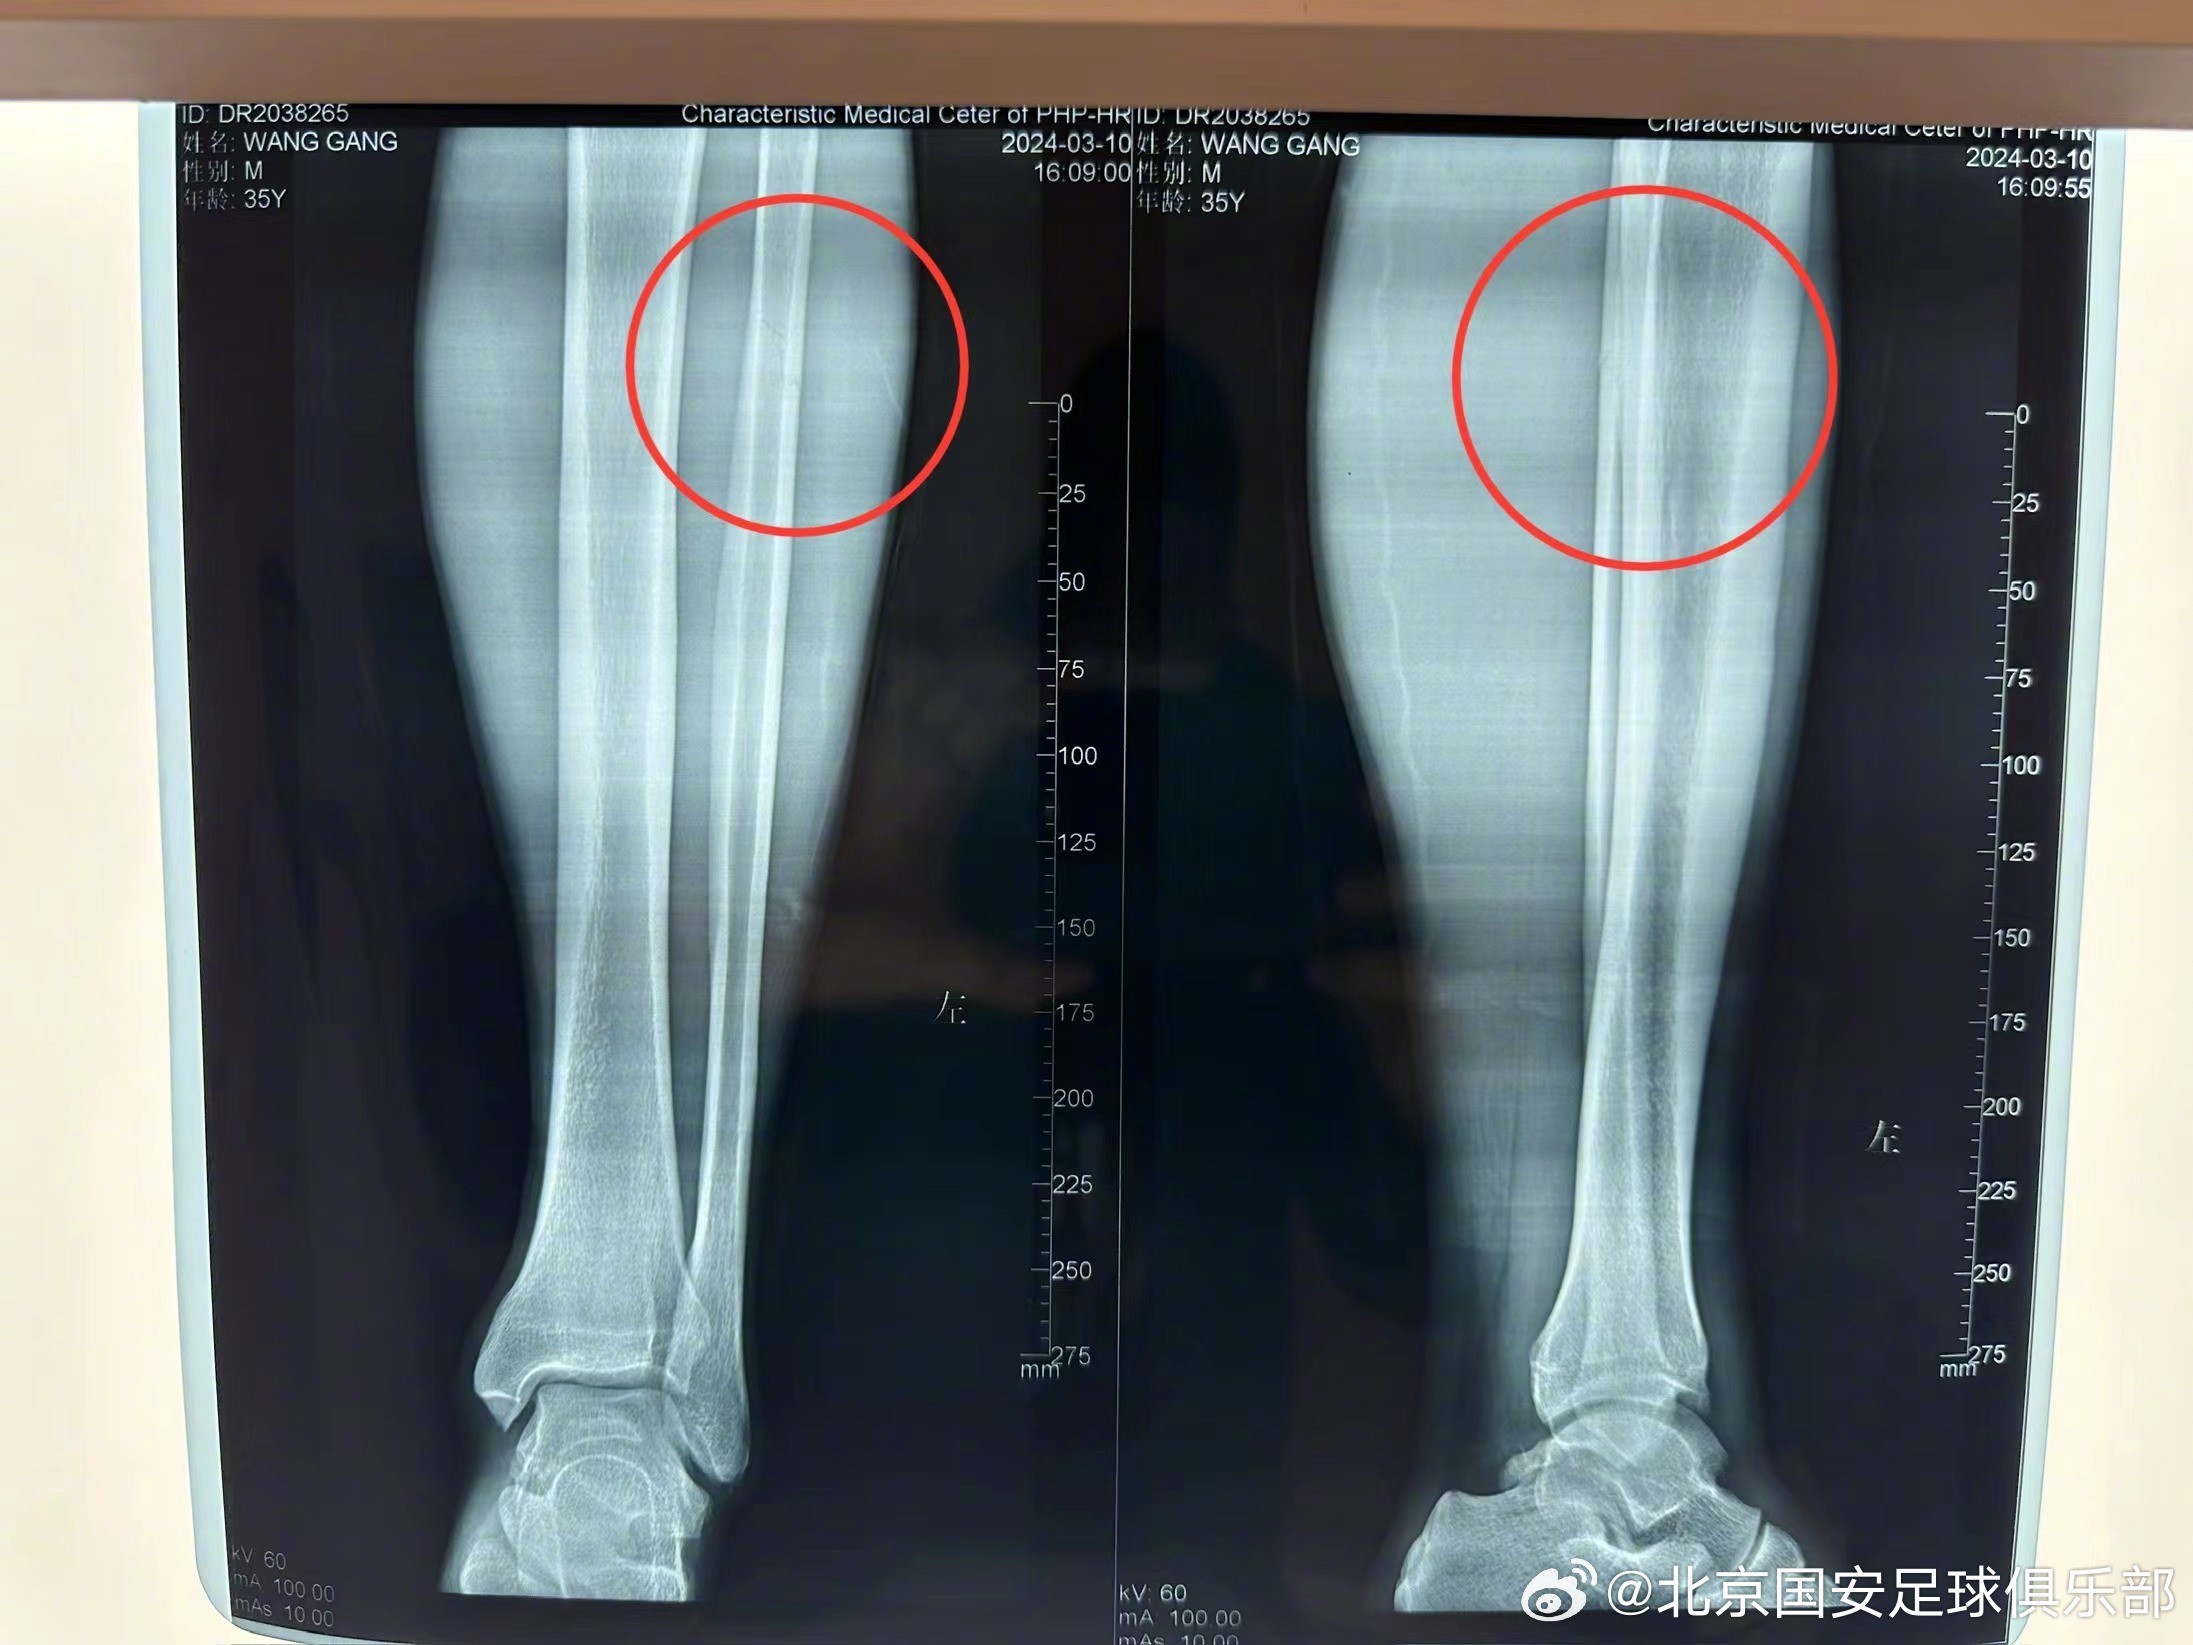

3月9日客场对阵山东泰山的比赛中,球员王刚在第49分钟时遭遇连续2次犯规,造成左小腿伤势,坚持11分钟后因疼痛无法进行比赛,离开赛场。

赛后经过医院X光检查,王刚左小腿中上段腓骨裂纹骨折(无移位)。结合北京积水潭医院专家会诊确定治疗方案,后续将进行小腿支具固定,免负重休息,并于6周后进行复查。